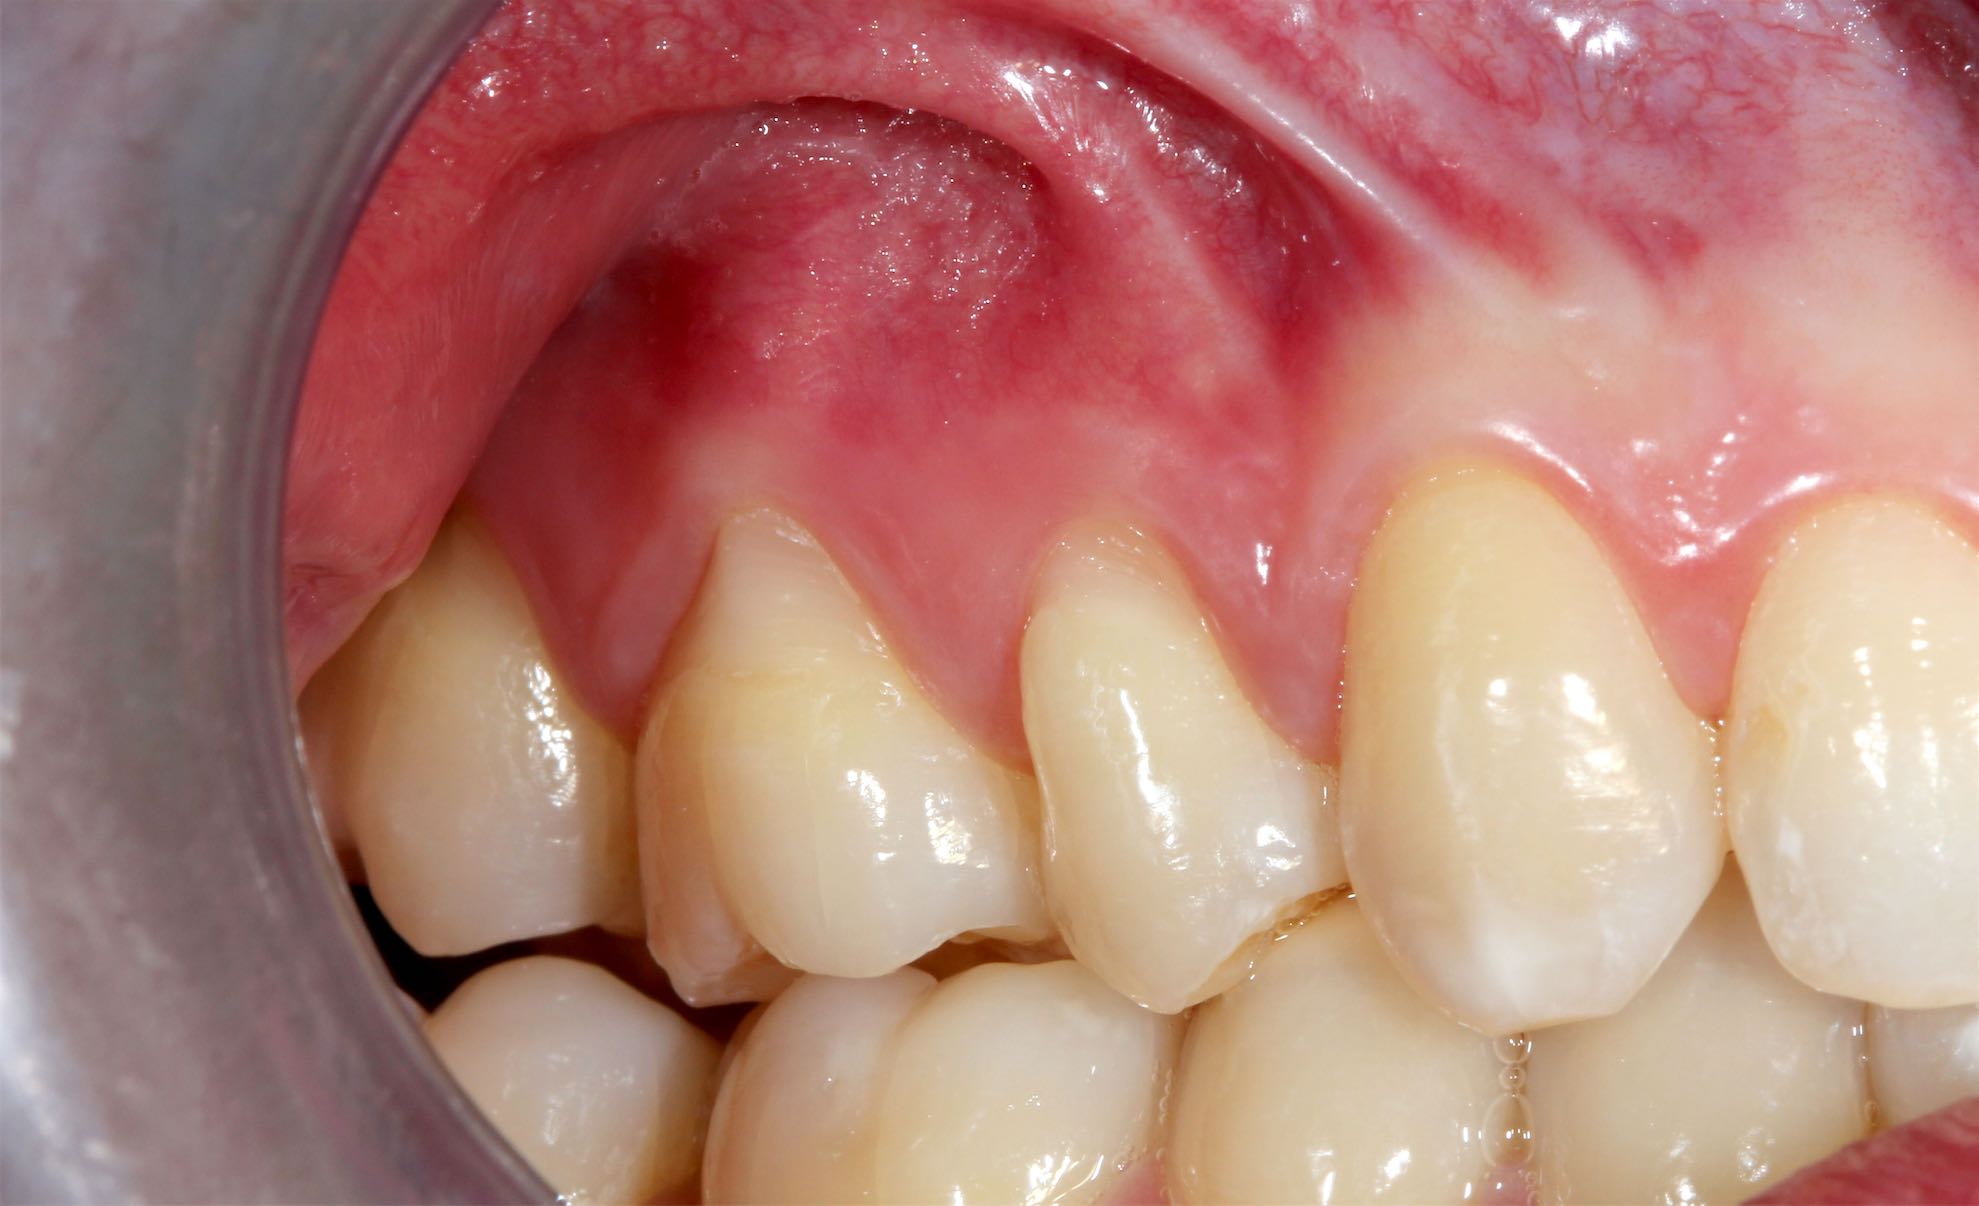

Periodoncia . Injertos de Encía

BeforeAfter